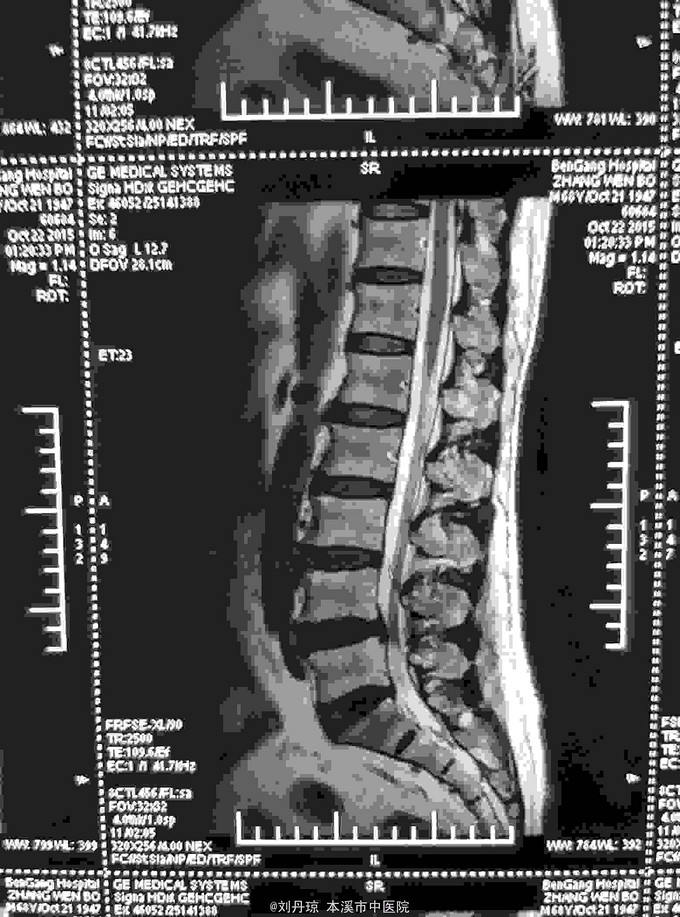

腰部间歇性钝痛伴左下肢放射痛麻木感半年。患者半年前无明显诱因感腰部间歇性钝痛伴左下肢放射痛麻木感,经多家医院治疗未见明显好转,今日来我院门诊求治,门诊医师以“ 腰椎间盘突出症、骶管囊肿 ”收入院治疗。

L4-S1棘突左侧1厘米压痛阳性,直腿抬高试验左40º右60º,加强试验左侧(阳性)右侧(阴性),腰椎功能障碍。左腿前外侧及足背外侧感觉减弱。 辅查CT: 腰椎间盘突出症、骶管囊肿

腰椎间盘突出症、骶管囊肿 治疗:骶管注射、甘露醇注射液静点、神经营养药物静点、小针刀治疗、中药熏药治疗、雷火灸治疗